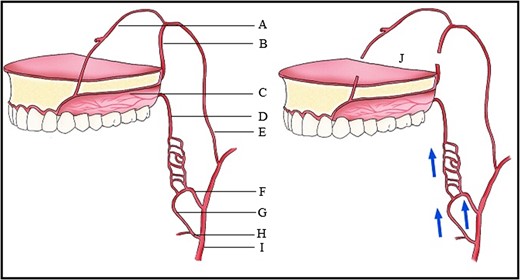

Blood supply of the maxilla. (A) Nasopalatine artery, (B) Descending palatine artery, (C) Greater palatine artery, (D) Lesser palatine artery, (E) Maxillary artery, (F) Ascending pharyngeal artery, (G) Ascending palatine artery, (H) Facial artery, (I) External carotid artery, (J) Le Fort I downfracture.

Blood flow to the maxilla is reduced by 50% in the first post-operative day after sacrifice of the descending palatine arteries [3]. However, there is excellent collateral blood supply particularly if only one artery is sacrificed, as in this case. Experimental studies have shown that loss of the descending palatine arteries results in a transient ischaemic period that is compensated for by a vascular proliferation that allows tissue healing. The collateral microvasculature from other vessels including the ascending pharyngeal and facial arteries (Fig. 1), maintains the viability of the palatine pedicle. The pedicle can withstand stretching greater than 10 mm of anterior repositioning of the maxilla.